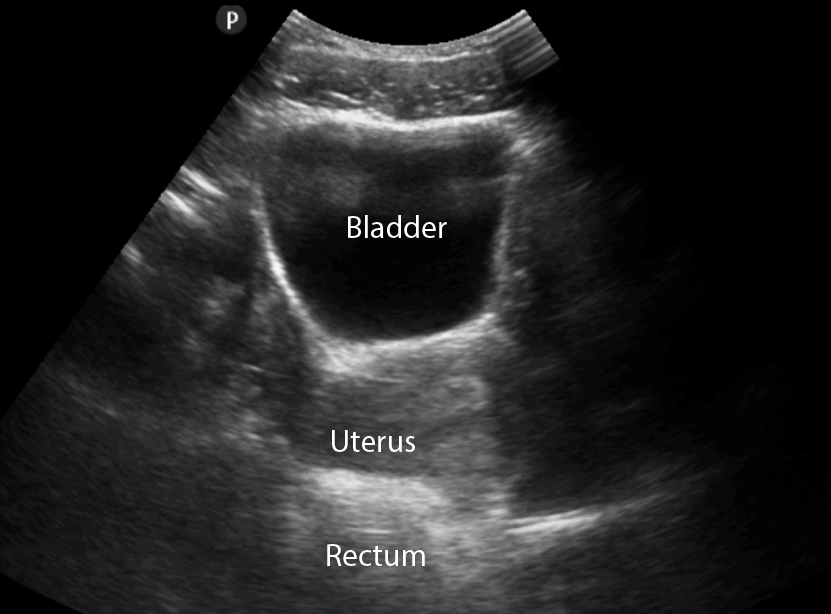

Longitudinal view: Female Bladder

Transverse view: Female Bladder